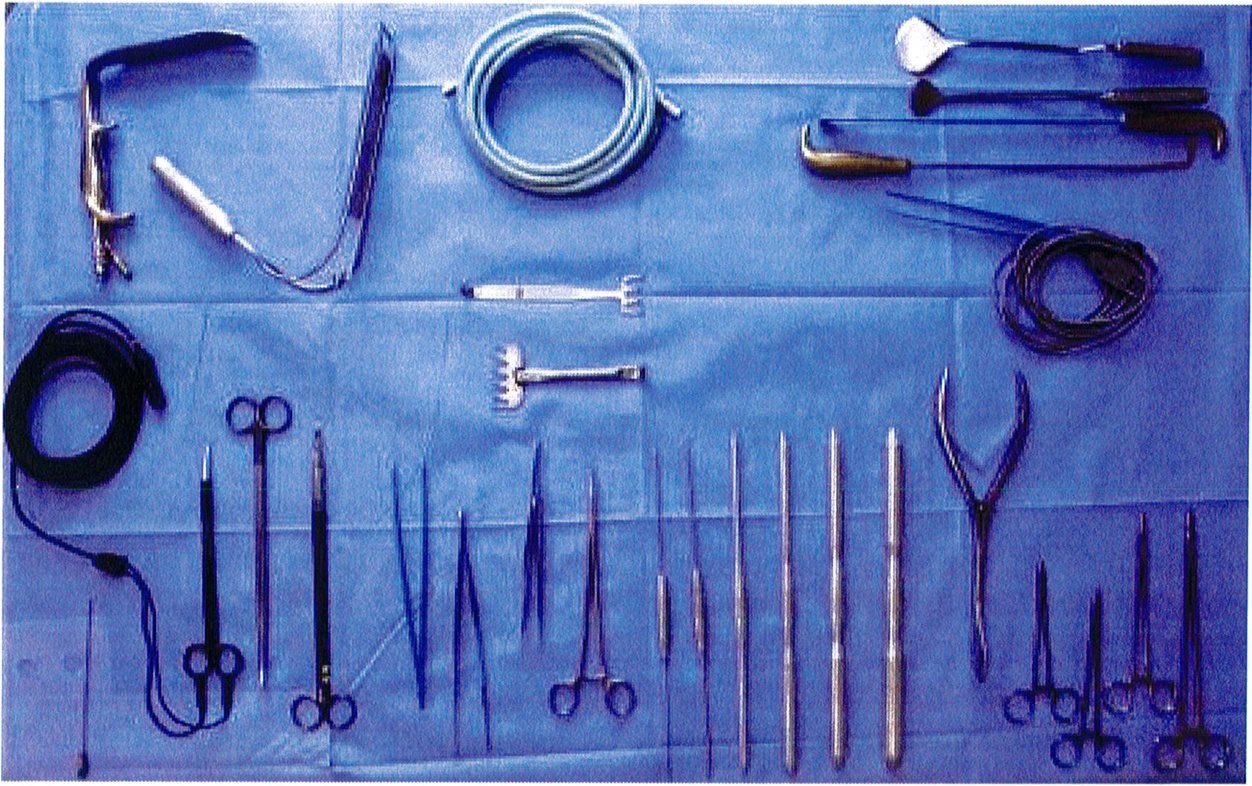

Dụng cụ hỗ trợ

Việc sử dụng implant, siz- ers và tiêu bản có sẵn cùng với kỹ thuật bóc tách phía bên ngoài bờ xương cùng đã giúp giảm đáng kể tỉ lệ biến chứng. Cuối cùng, việc sử dụng các dụng cụ phẫu thuật đặc biệt đã giúp công đoạn bóc tách trở nên dễ dàng hơn, giảm tỉ lệ tử vong cũng như thời gian phẫu thuật.